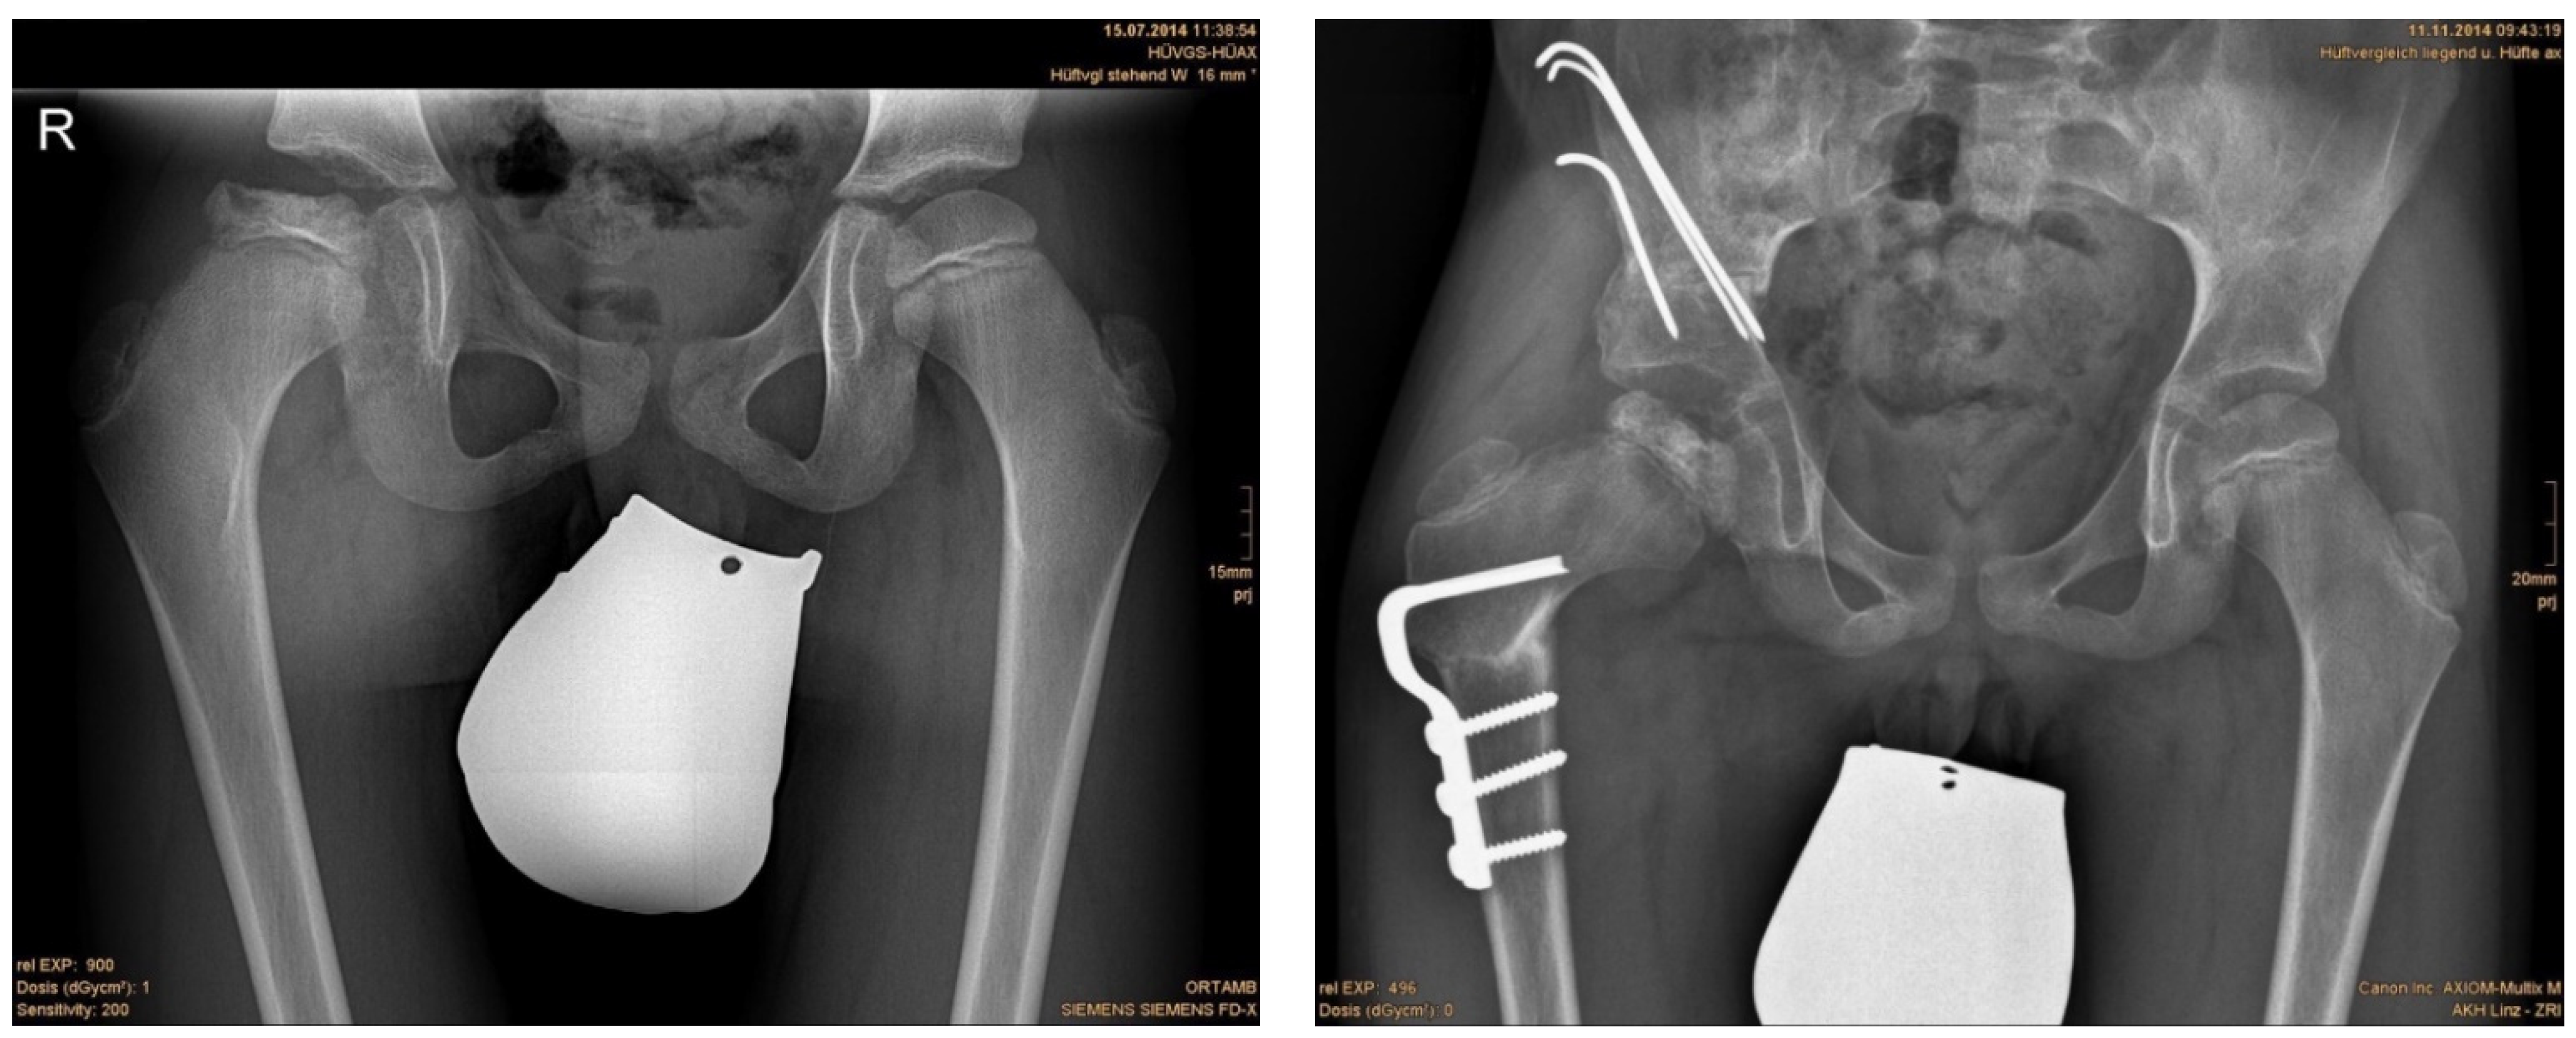

Three months after surgery, children with DDH showed significant decreased RMI compared with children with NDH in a two-sample Student’s t-test (2.77 ± 6.90% vs. 12.94 ± 13.50%; p = 0.011). More often an osteotomy of the iliac bone (Salter innominate, Pemberton, Chiari) was carried out in patients with DDH than with NDH (27 vs. 17; p < 0.001). In cases with combined one step iliac and femoral osteotomy, the residual RMI was significantly lower than in cases with osteotomy of the femur alone (7.02 ± 11.1% vs. 16.85 ± 4.71%; p < 0.001) (Table 4, Figure 1 and Figure 2).

Figure 1. (left) Anteroposterior radiograph of a six-year-old male with NDH; (right) result 3 months postoperatively.